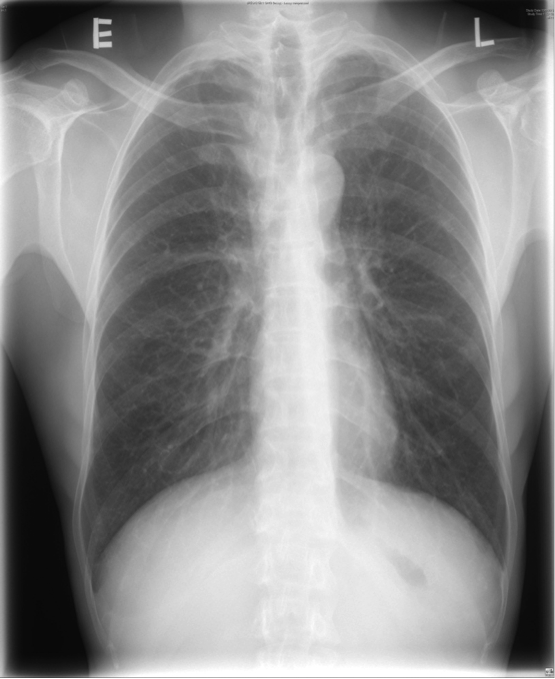

A 56 year old housewife, who was a non-smoker and non-drinker, presented with dry cough for three months. She denied other complaint and she enjoyed a good past health. Her physical examination was unremarkable. Her chest X-ray (CXR) showed patchy infiltrates in bilateral lower zones and several lung nodules bilaterally (Fig 1). Her initial blood tests including complete blood picture, renal & liver function test, erythrocyte sedimentation rate, urate, lactate dehydrogenase and tumor markers (including carcinoembryonic antigen, alpha-fetoprotein, CA 15.3, CA 19.9 and CA 125) were normal. Her sputum was negative for culture, acid fast bacilli and cytology. Her urine routine microscopy was also normal. Contrast computer tomography (CT) thorax showed bilateral lung nodules with size 0.5-2cm, bilateral thin walled lung cysts with size 0.5-2.5cm and sub-segmental collapse of right middle lobe. Some of the nodules had speckles of calcifications inside (Fig 2A, 2B). Fibre-optic bronchoscopy and transbronchial biopsy (FOB+TBBx) were not diagnostic. We had discussed with her about different investigation options included positron emission tomography (PET)-CT and repeating biopsy by FOB+TBBx under fluoroscopy guidance or CT guided fine needle aspiration (FNA). She opted for PET-CT. Her PET-CT was reported as “There were multiple hyper-metabolic nodules (maximum standardized uptake value (SUVmax ) 4.4). They were suspicious of metastases.” There were also multiple hypo-metabolic lucent cystic lesions scattered on both lungs. A complex cystic mass with calcification and some F-18 fluorodeoxyglucose (FDG) avidity was found incidentally at the right adnexal region (Fig 3A, 3B). At that juncture, the working diagnosis was gynaecological malignancy with multiple lung metastases. FOB+TBBx repeated under fluoroscopy guidance showed nodular deposition of extracellular amorphous eosinophilic material in the alveolar spaces. These depositions were salmon pink in Congo red section, and they showed yellow-green birefringence in polarized microscopy. The histological feature was compatible with amyloid. Total abdominal hysterectomy and bilateral salpingo-oophorectomy was done by the gynaecologist and the right adnexal lesion was found to be a mature ovarian teratoma with thyroid tissue. Thus the right ovarian teratoma was just an incidental finding and was not related to the amyloidosis. Further assessment and workup were done to look for possible condition that was known to be associated with amyloidosis such as chronic inflammatory diseases and monoclonal plasma cell dyscrasias. Further enquiry revealed she had chronic dry mouth for over 10 years. Her antinuclear antibody (ANA) titer was raised (1/640) and her anti-Ro (SS-A) titer was positive. Her schirmer test was 0mm over both eyes, indicating severe dry eye. Although the histology of her salivary gland biopsy was reported as within normal limit, she was considered as a case of primary Sjogren’s syndrome by the rheumatologist and symptomatic treatment was provided. Clinically, no other organ was involved by the amyloidosis. Thus the final diagnosis was nodulocystic pulmonary amyloidosis associated with primary Sjogren’s syndrome. An interval CT thorax about two years later showed no significant interval change.

FIgure 1